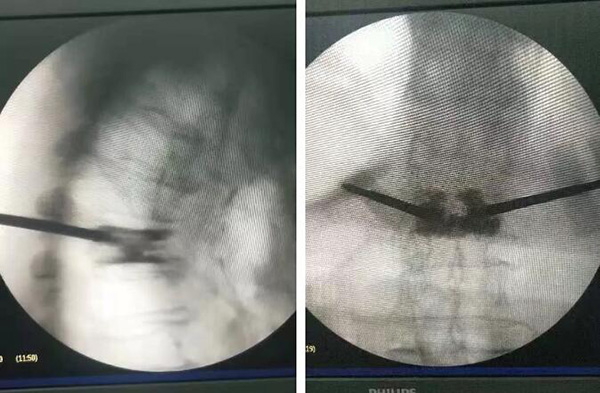

10月29日手術(shù)現(xiàn)場

廣安醫(yī)院脊柱科戈才華主任親自主刀,在局部麻醉的情況下,為陳爺爺實施了“胸7/腰1椎體壓縮性骨折經(jīng)經(jīng)皮穿刺球囊擴張椎體成形術(shù)。”

經(jīng)過一個半小時,手術(shù)順利完成。術(shù)后脊柱科醫(yī)護人員對陳爺爺精心護理,“手術(shù)后最開始幾天,我父親情緒很不穩(wěn)定,你們的主任、醫(yī)生、護士長都積極安慰鼓勵她,我父親恢復的這么好多虧了你們,真心的感謝你們醫(yī)院”陳爺爺?shù)膬鹤舆@樣說。